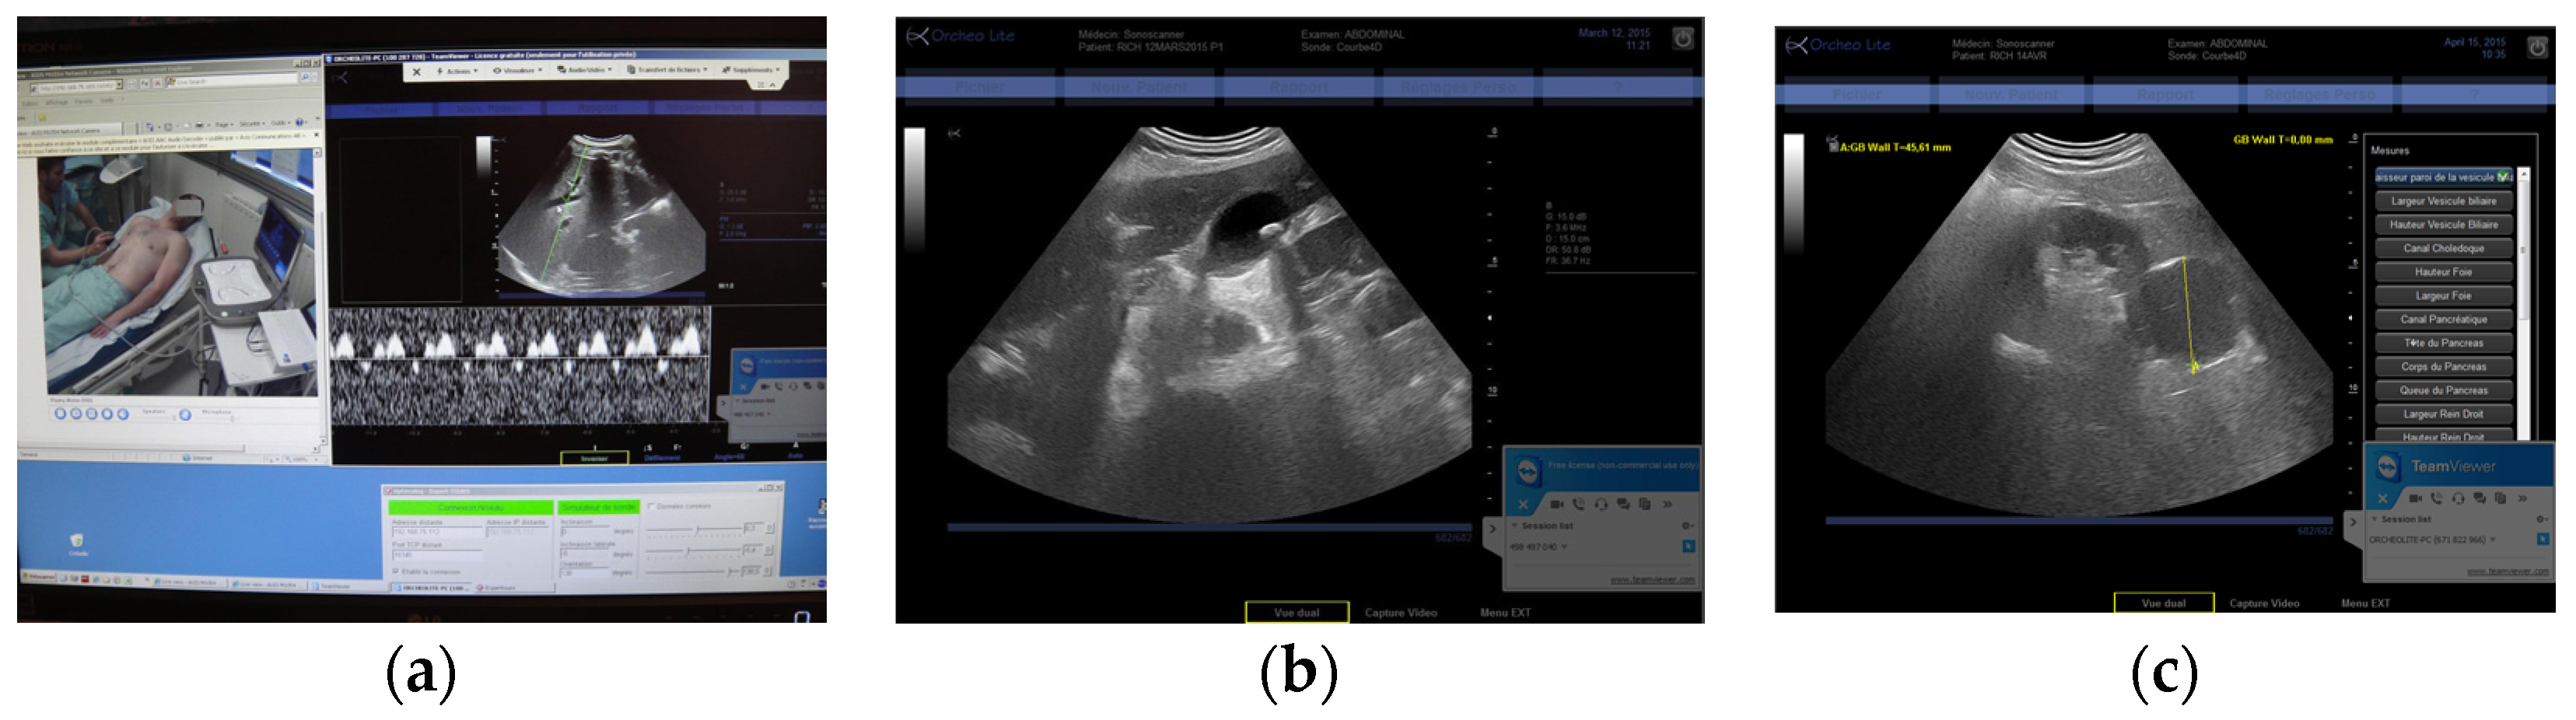

Figure 2. (a) RA expert center computer screen with video of the patient (left) and echographe screen (right); (b) Renal cyst image obtained using RA; (c) Carotid bifurcation with atheromatous plaque in color Doppler using RG.

The three tele-echography methods used included: (a) a teleoperated robotic arm (RA) holding an ultrasound probe; (b) a teleoperated echograph with a motorized probe system (MP); and (c) remote guidance (RG). The RA (Figure 1) system consisted of a large structure that held a standard ultrasound probe. From the expert center (Figure 2), a trained sonographer performed the tele-echography examination by manipulating a dummy probe which teleoperated the robotic arm [1,3]. Throughout the examination, the non-sonographer operator at the patient site was required to position the robotic arm over the patient and to adjust the echograph functions and settings as directed by the trained sonographer. The second system of tele-echography, MP, consisted of a modified commercial echograph with motorized probes [2]. The ultrasound probes used for this system contained internal motors to tilt and rotate the probe transducer which the trained sonographer teleoperated from the expert center (Figure 3 and Figure 4). In addition to controlling the probe orientation, the echograph used for this system was modified to allow for the teleoperation of settings and functions. The final system of remote echography evaluated utilized RG (Figure 5) [5,6,7]. For this system, the non-sonographer (GP) had the probe in hand and performed the echographic examination as directed by a trained sonographer via videoconference.

A summary of the organs examined and the method used for each examination is presented in Table 1. Both the RA and the MP systems provided enough views of the deep organs of interest to deliver diagnoses in 97% of the cases (Figure 2 and Figure 4). For the superficial targets (organs and vessels), MP (Figure 4) and RG (Figure 5) provided the correct view of the organ necessary for the diagnosis in 98% of cases. Overall, tele-echography was not able to return enough information for a safe diagnosis in 11 of the 340 examinations (3.2%). These 11 cases involved imaging of deep organs (gall bladder, spleen, pancreas) on obese patients or patients with very poor echogenicity, and imaging of leg veins (femoral, tibial, gastrocnemius veins) on patients with substantial leg edema. For each of these cases, patients were referred to other medical centers for standard echography examinations.